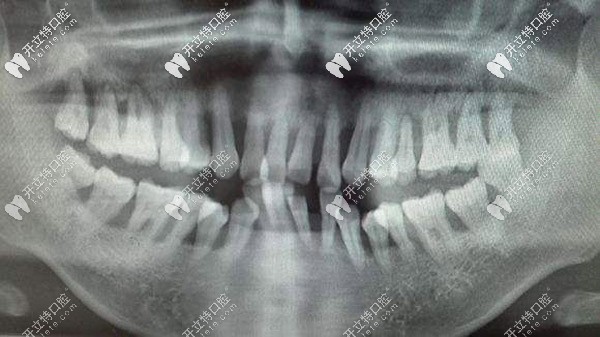

這就是侵襲性牙周炎的牙片

這就是侵襲性牙周炎的牙片▲